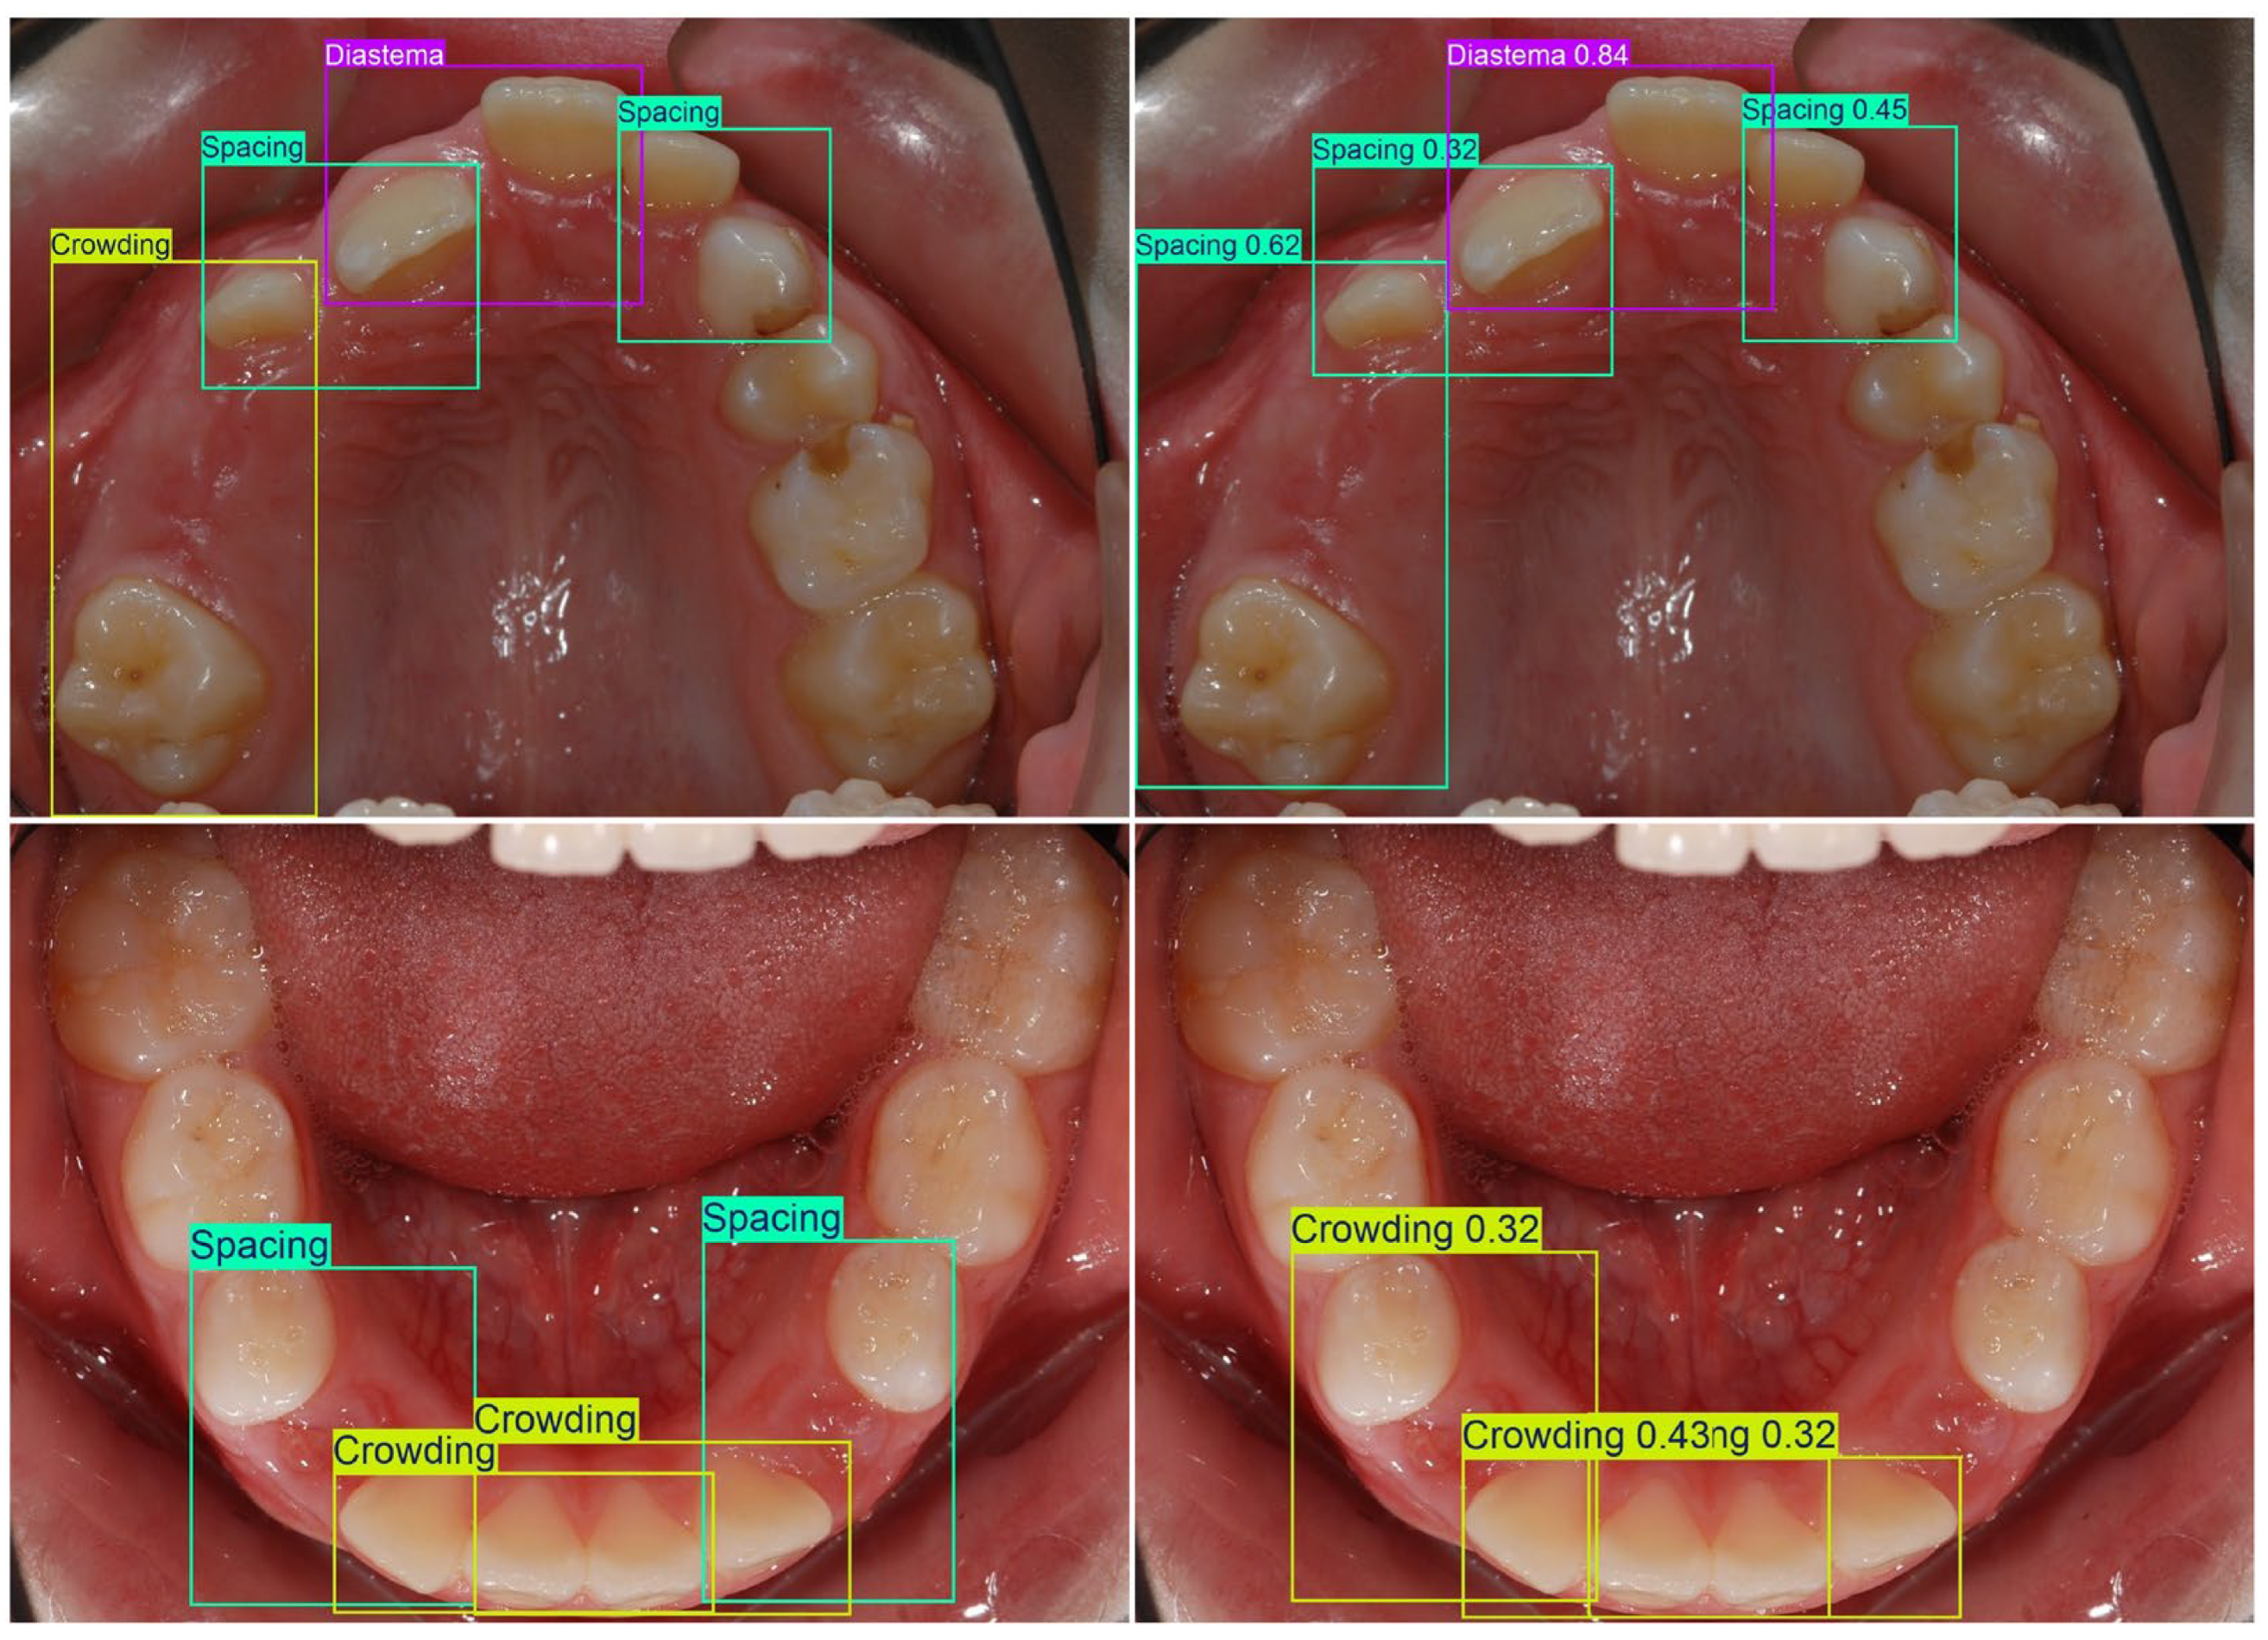

| Crowding | BB over the affected tooth as well as the two adjacent teeth |

| Spacing | BB over the existing gap as well as the two adjacent teeth |

| Diastema | BB over the upper central incisors |

| Crowding | Insufficient space in the arch, causing overlapping, rotations, or displacement of teeth |

| Diastema | A distinct midline gap between the maxillary central incisors, beyond normal contact separation |

| Spacing | When no contact point was present and gingiva was visible between the teeth; midline diastema was excluded |